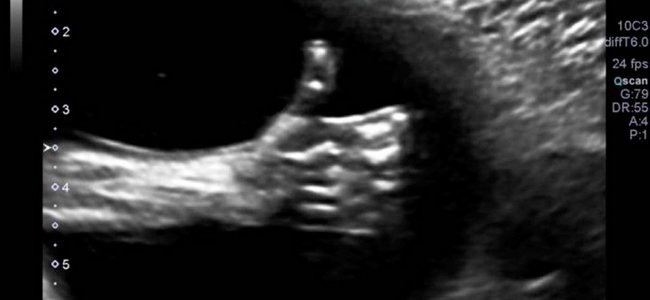

Um bebê manda um ‘eu curto’ aos seus pais do útero materno

Foi uma grande casualidade, mas Nicole Kim, uma mamãe canadense que ao fazer uma ecografia rotineira recebeu uma grande surpresa. O médico aproximou a imagem do bebê e acabou pegando uma imagem instantânea que ela se lembrará para sempre: o bebê tinha o seu punho fechado e o dedo polegar levantado. É o clássico gesto de ‘ok’ que se popularizou no Facebook.

A alegria foi enorme para Kim, já que estava passando por um momento delicado porque o seu marido tinha sido despedido do seu trabalho. Para eles o ‘eu curto’ de que tudo vai sair bem a partir de então. A imagem, é claro, se tornou um viral desde o momento que decidiram publicá-la.